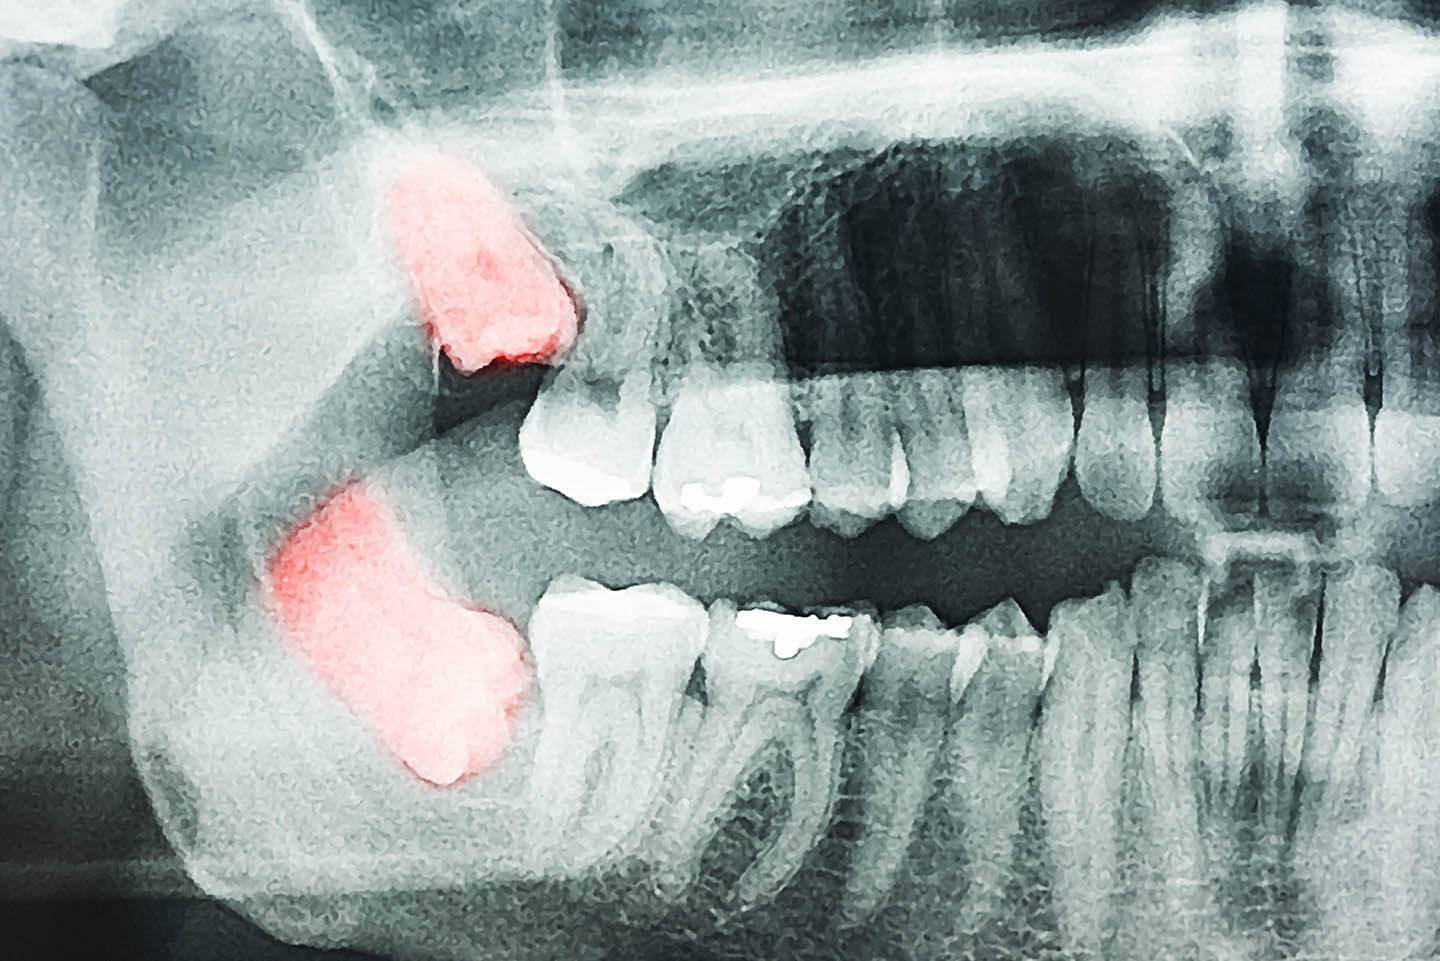

If your wisdom teeth are impacted and haven’t fully erupted through the gums, a simple extraction may not be possible. In these cases, a surgical extraction is needed. This involves making a small incision in the gum, sectioning the impacted tooth into smaller pieces, and carefully removing them through the opening.

At The Burkitt Center, we use the latest surgical techniques and offer multiple sedation options to keep you comfortable throughout the procedure. As a biologically focused practice, we prioritize tissue preservation, reduced inflammation, and a smoother recovery.